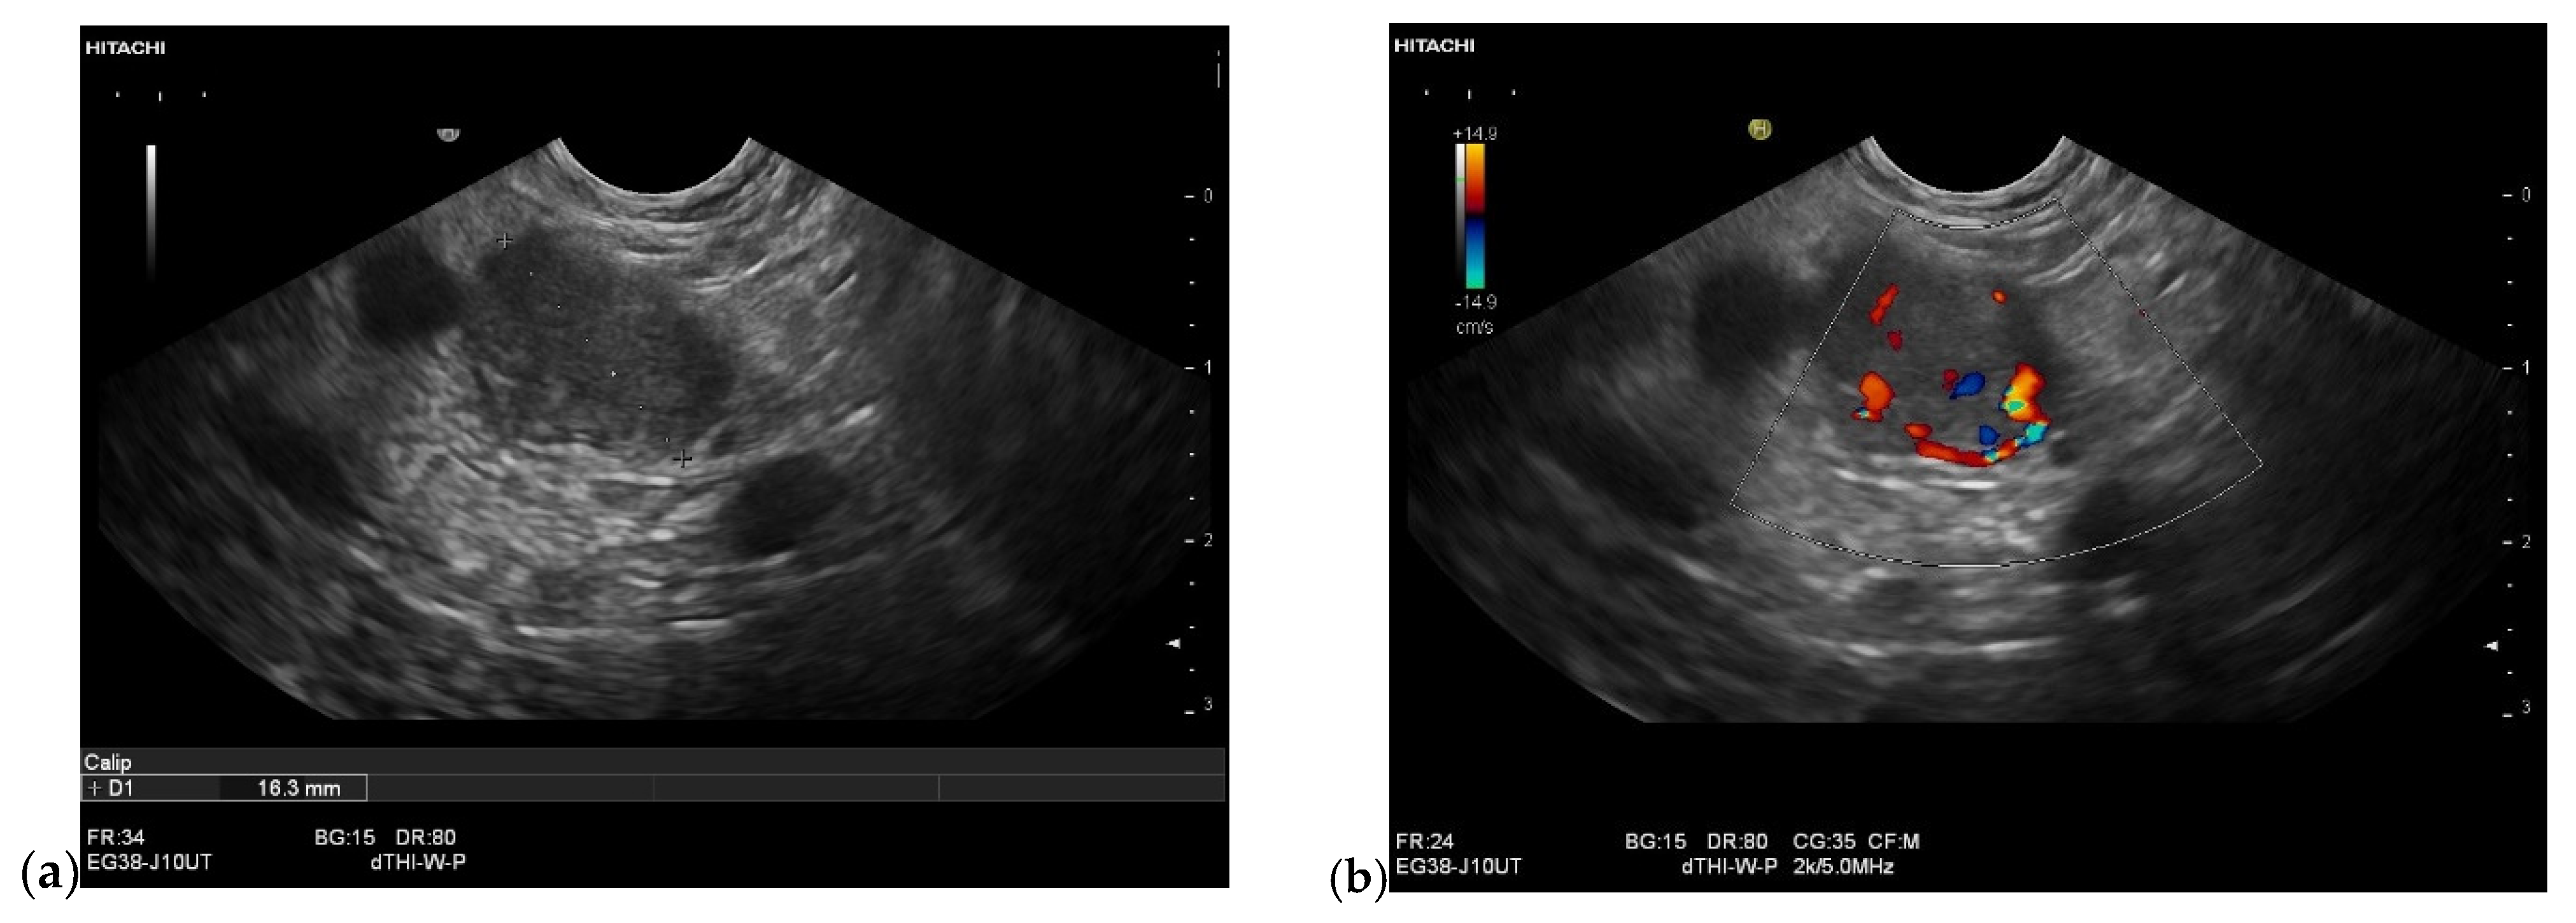

3.4. CEUS and CH-EUS

B-mode US/EUS

| Mostly hypoechoic, homogeneous, or heterogeneous More likely well-defined borders (46%) Anechoic and hyperechoic lesions are possible | Hypoechoic, typically heterogeneous, irregular borders | Hypoechoic, mostly homogeneous, smoothly bordered. Cystic components or cystic solid PanNENs are possible |

| Variable, in 80% no pancreatic duct dilatation | Pancreatic duct stenosis and pancreatic duct dilatation are an early and typical feature | No pancreatic duct dilatation |

| Mostly no infiltration into adjacent vessels | Infiltration around and into the vessels | No infiltration into adjacent vessels |

| Colour Doppler Imaging | RCC metastases are hypervascularized Most other pancreatic metastases are hypovascularized | No hypervascularization | Hypervascularized |